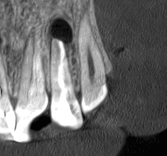

For more than a year, the patient had a persistent fistula near the upper lateral incisor. The tooth had already been retreated through the root canal at another clinic, but the inflammation kept returning. An infection remained at the root tip, and extraction was becoming a real possibility.

We decided to perform microsurgery. Through a small, precise access point, we carefully removed the воспалatory lesion at the root tip, cleaned the affected tissues, and sealed the area securely. The goal was to eliminate the source of infection while preserving the natural tooth.